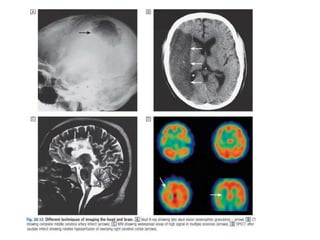

Modalities

• X-Ray

CXR

Plain abdominal x-ray

• Computed tomography

• Magnetic resonance

imaging

• Ultrasound

• Nuclear imaging

Modalities • X-Ray CXR Plain abdominalx-ray • Computed tomography • Magnetic resonance imaging • Ultrasound • Nuclear imaging